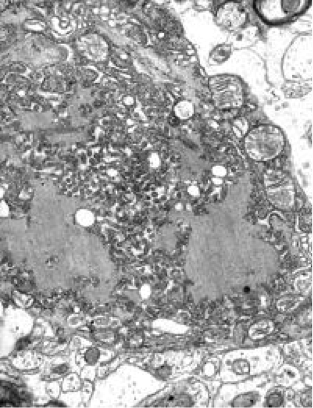

狂犬病にかかっているイヌでは、狂暴で興奮して甲高い鳴き声を上げることが多くみられ、発症後3~15日で死亡します。脳組織を採取して神経の細胞質中にウイルスの封入体を証明することにより診断が確定します。